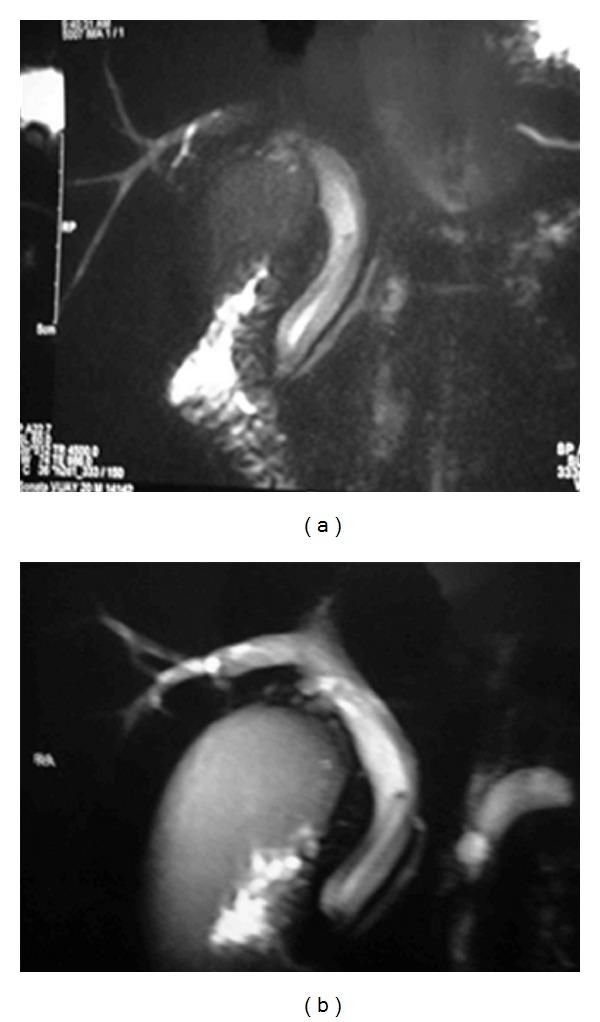

Ascariasis is one of the most common helminthic diseases in humans, occurring mostly in countries with low standards of public health and hygiene, thereby making ascariasis highly endemic in developing countries. In endemic areas, 30% of adults and 60-70% of children harbour the adult worm. Biliary ascariasis is a rare cause of obstructive jaundice. Conventional management involves endoscopic extraction of worm. We are reporting a rare case of ascaris which induced extrahepatic biliary obstruction in a young male who presented with acute cholangitis. The ascaris was removed by laparoscopic exploration of the common bile duct. Postoperative period was uneventful.

蛔虫病是人类最常见的蠕虫病之一,主要发生在公共卫生和卫生标准较低的国家,因此在发展中国家蛔虫病高度流行。在流行地区,30%的成年人和60%-70%的儿童体内有成虫。胆道蛔虫病是梗阻性黄疸的罕见病因。传统治疗方法是通过内镜取出蛔虫。我们报告了一例罕见的蛔虫病例,该病例导致一名患有急性胆管炎的年轻男性出现肝外胆管梗阻。通过腹腔镜探查胆总管取出了蛔虫。术后恢复顺利。

Biliary ascariasis: MR cholangiography findings in two cases.胆道蛔虫病:两例磁共振胰胆管造影表现

MR imaging features of biliary ascariasis.胆道蛔虫病的磁共振成像特征。